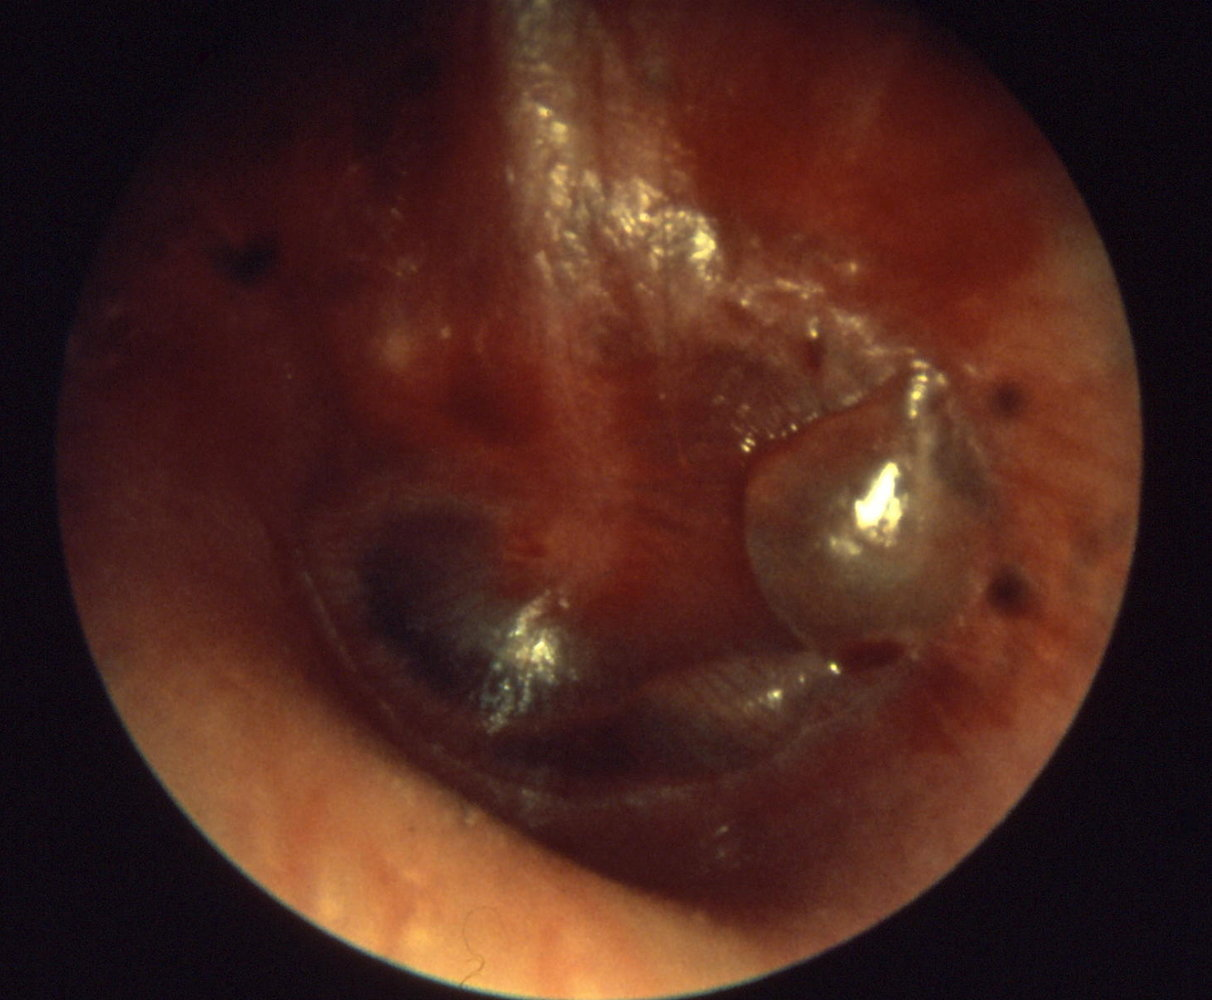

Bullous myringitis (type of AOM)

Can be mistaken for herpes zoster oticus (Ramsay Hunt)

The tympanic membrane shows erythematous changes with visible isolated hemorrhagic infiltrates (dark spots)